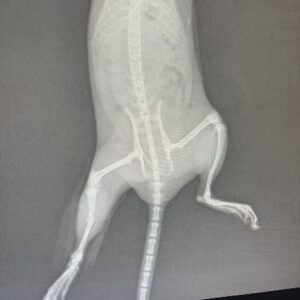

I knew the injury was far beyond my ability to treat. I rushed her to Vets One in Crimplesham, where the team were incredibly kind and supportive. After surgery to suture the wound, X-rays showed a dislocated hip and fractures to the tibia and fibula in her leg. We discussed her welfare carefully – if there was a chance without her suffering, we would try.

Laura and her team achieved something remarkable. They fashioned a tiny anaesthetic mask, reset her hip, straightened her leg and applied a cast. Laura later told me she had never performed a procedure like this on such a small animal. Starboard recovered quickly from the anaesthetic, though the hip was a concern as repeated dislocation would have caused pain and limited mobility.